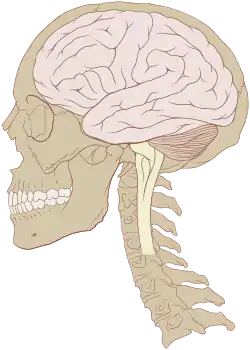

The human brain is the central organ of the human nervous system, and with the spinal cord makes up the central nervous system. The brain consists of the cerebrum, the brainstem and the cerebellum. It controls most of the activities of the body, processing, integrating, and coordinating the information it receives from the sense organs, and making decisions as to the instructions sent to the rest of the body. The brain is contained in, and protected by, the skull bones of the head.

The cerebrum, the largest part of the human brain, consists of two cerebral hemispheres. Each hemisphere has an inner core composed of white matter, and an outer surface – the cerebral cortex – composed of grey matter. The cortex has an outer layer, the neocortex, and an inner allocortex. The neocortex is made up of six neuronal layers, while the allocortex has three or four. Each hemisphere is conventionally divided into four lobes – the frontal, temporal, parietal, and occipital lobes. The frontal lobe is associated with executive functions including self-control, planning, reasoning, and abstract thought, while the occipital lobe is dedicated to vision. Within each lobe, cortical areas are associated with specific functions, such as the sensory, motor and association regions. Although the left and right hemispheres are broadly similar in shape and function, some functions are associated with one side, such as language in the left and visual-spatial ability in the right. The hemispheres are connected by commissural nerve tracts, the largest being the corpus callosum.

The cerebrum is connected by the brainstem to the spinal cord. The brainstem consists of the midbrain, the pons, and the medulla oblongata. The cerebellum is connected to the brainstem by three pairs of nerve tracts called cerebellar peduncles. Within the cerebrum is the ventricular system, consisting of four interconnected ventricles in which cerebrospinal fluid is produced and circulated. Underneath the cerebral cortex are several important structures, including the thalamus, the epithalamus, the pineal gland, the hypothalamus, the pituitary gland, and the subthalamus; the limbic structures, including the amygdala and the hippocampus; the claustrum, the various nuclei of the basal ganglia; the basal forebrain structures, and the three circumventricular organs. The cells of the brain include neurons and supportive glial cells. There are more than 86 billion neurons in the brain, and a more or less equal number of other cells. Brain activity is made possible by the interconnections of neurons and their release of neurotransmitters in response to nerve impulses. Neurons connect to form neural pathways, neural circuits, and elaborate network systems. The whole circuitry is driven by the process of neurotransmission.

The brainstem, resembling a stalk, attaches to and leaves the cerebrum at the start of the midbrain area. The brainstem includes the midbrain, the pons, and the medulla oblongata. Behind the brainstem is the cerebellum (Latin: little brain).[8]